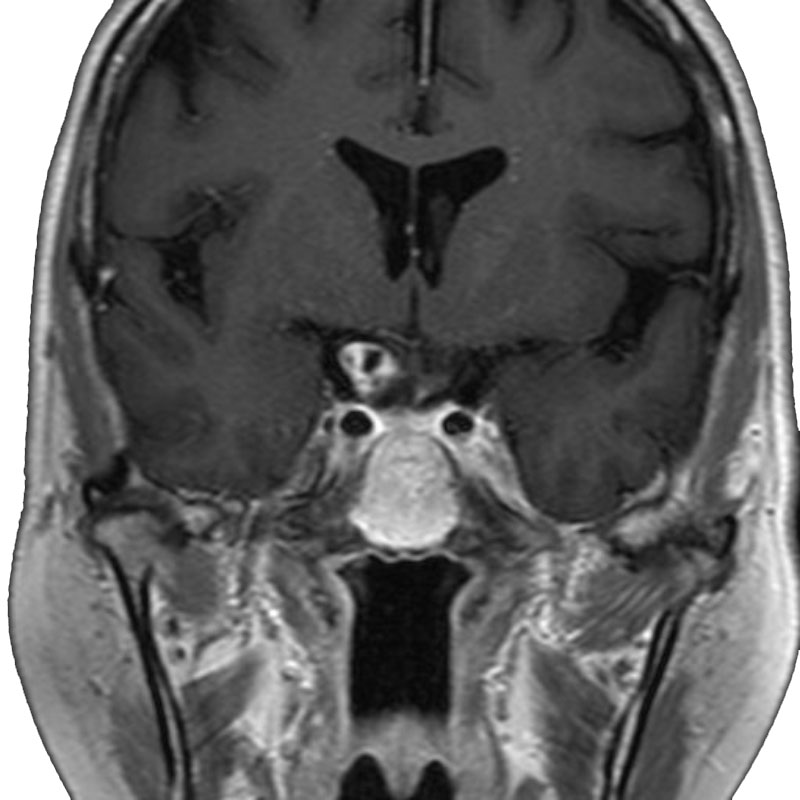

三叉神経鞘腫

摘出術

南田/野本